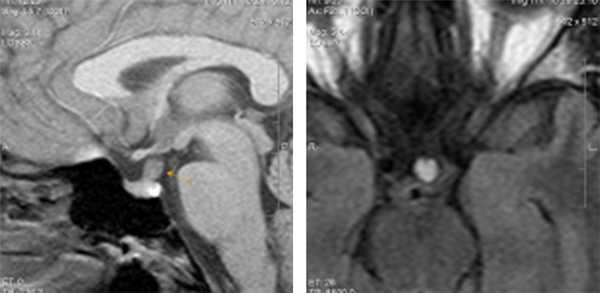

В центр МРТ Эксперт Воронеж обратилась пациентка, 31 год, с жалобами на головные боли справа и чувство тяжести в правых отделах шеи. Других жалоб пациентка не предъявляла, клинико-лабораторных данных о наличии дисфункции гипоталамо-гипофизарной системы предоставлено не было.

При проведении МРТ головного мозга

было выявлено умеренно выраженное утолщение и повышение интенсивности МР-сигнала от воронки гипофиза. Других изменений в проекции гипофиза, гипоталамуса, параселлярных областей не визуализировалось. Помимо этого, были обнаружены очаги глиоза больших полушарий головного мозга.

Данная картина в виде утолщения ножки гипофиза с достаточно четкими ровными контурами и повышение интенсивности МР-сигнала от нее характерна для заболевания воспалительной этиологии – лимфоцитарного гипофизита (когда происходит вовлечение в процесс воронки гипофиза, но при этом остаются интактными другие отделы гипофиза – адено- и нейрогипофиз). Среди других нозологий были выделены: а) инфундибулит другой этиологии, например при гранулематозном воспалительном процессе - саркоидозе б) вместе с тем, данные только МР-томографического исследовния, без достаточно четких клинико-лабораторных данных, не позволяют исключить и неопластического процесса данной локализации, в частности герминомы; в) гамартома гипоталамуса также выставлялась нашими докторами в дифференциально-диагностический ряд; г) метастатическое поражение воронки гипофиза.

из выстроенного дифференциального ряда врачи исключили гамартому (поскольку для данной патологии характерны другие сигнальные характеристики при МР-исследовании, клинически она проявляется преждевременным половым созреванием, насильственным смехом и плачем,чего не было в данном случае). Также из диф. ряда было исключено метастатическое поражение воронки (четкость и ровность контуров, симметричность, однородность, отсутствие узловатых утолщений – нехарактерные признаки для метастаза).

Дальнейшая дифференциальная диагностика

проводилась между гипофизитом (воспалительным процессом) и изменениями неопластического характера. В результате пришли к выводу, что выявленные изменения более специфичны для изменений воспалительного характера - лимфоцитарного гипофизита (в виде изолированного гипофизита). Но при этом полученная МР-картина не позволяет полностью исключить и неопластического процесса воронки гипофиза (герминомы) – что менее вероятно с учетом клинических данных и результатов внутривенного контрастирования.

Что дал метод МРТ в данном случае:

возможность выявить небольшой по размерам участок изменений в головном мозге, в воронке гипофиза (максимальный размер утолщенной воронки гипофиза всего 0,7 см), но при этом крайне важные клинически изменения, требующие дальнейшего наблюдение и, возможно, морфологической верификации .